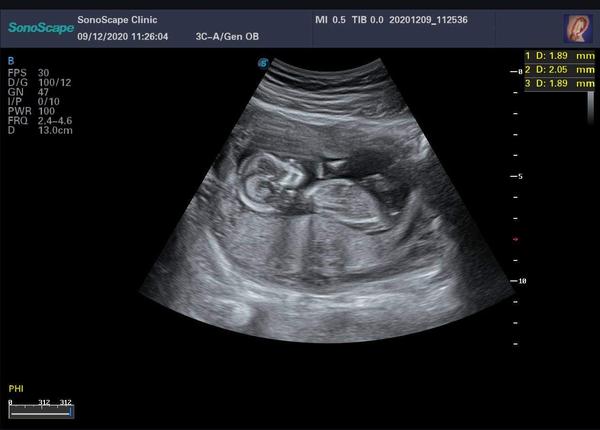

Velikost miminka ve 12. týdnu. Jak velké bylo to vaše?

Dobrý den, poslední MS byla 3.9.2020. Původně mi lékař určil termín porodu na 10.6. Nyní jsem byla na 1. screening A bylo nás tam celkem 6 maminek takže byl zmatek. Nyní bych měla být 15tt. Lékař, ale řekl, že to bude spíše 12 týden. Miminko má dle ultrazvuku 13 cm. A dle 3D ultrazvuku 10cm. To mě přijde, ale nějak hodně na 12 týden. Kolik mělo Vaše miminko ve 12 TYDNU? Děkuji za odpovědi.

Na screeningu v 12+3 6 cm

Ono taky velmi záleží, jak moc přesně dokáže embryo doktor změřit, takže se to klidně může pár dnama lišit. Já měla v 12+1 velikost 6,3cm. Spíš než na velikost, bych se zaměřila na výsledky screeningu 😉

Já byla včera na první utz,12+1tt miminko 11,8cm.

Byla jsem na 1. Screeningu 12+3tt a miminko mělo 12,9cm. Vše bylo ok